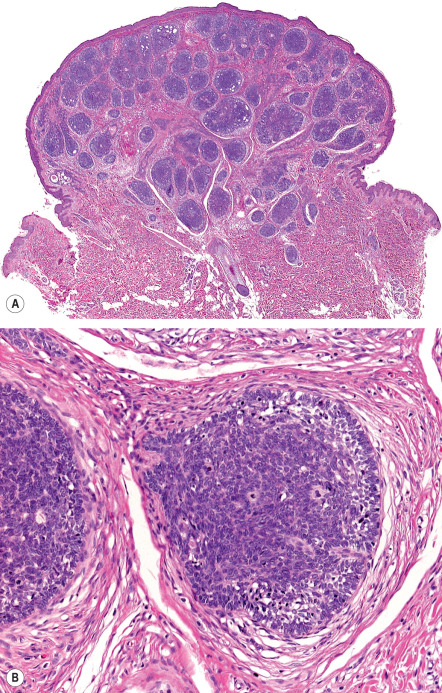

All trichoepitheliomas and trichoblastomas have in common the architectural attributes of a benign neoplasm – namely, relative symmetry, circumscription, and a lack of substantial cytologic atypicality. In addition, all are linked by prominence of follicular germinative cells with enveloping fibrocytic stroma that varies in degree . In classic trichoepithelioma, the fibrocytic stroma is conspicuous and constitutes as much as half of the cellularity of the lesion in a given cross-section. In other lesions that simulate BCC, follicular germinative cells may be arrayed as either small or large nodules with only scant intervening sclerotic stroma. The coarse fibrous stroma typically maintains tightly adherent contact to the lesional follicular germinative cells . This is in distinct contrast to the pattern of BCC, in which clefts between basaloid cells and stromal elements often serve as a diagnostic clue.

In classic trichoepithelioma, follicular germinative cells are often disposed as small clusters or as reticulate and cribriform cords ( Fig. 111.13 ). There are usually foci of pronounced bulbar differentiation, emulating the follicular bulb and papilla; these structures have been termed papillary mesenchymal bodies . Classic trichoepithelioma does not typically show follicular germinative differentiation exclusively. Rather, small cornifying cystic spaces with surrounding pinkish keratinocytes, reflecting concurrent infundibular or isthmic differentiation, are also apparent.

In small or large nodular trichoblastoma, follicular germinative cells comprise the majority of the surface area, papillary mesenchymal bodies may be inconspicuous, and superficial follicular differentiation may be absent. Trichoblastic fibroma is a designation used to characterize small nodular trichoblastomas with exaggerated fibrous stroma that often constitutes over half of the cross-sectional area of the lesion . Papillary mesenchymal bodies may be conspicuous in trichoblastic fibroma. With close scrutiny, other modes of differentiation can occasionally be found in a trichoblastoma. There may be tiny collections of mature sebocytes, reflecting concurrent sebaceous differentiation, and (apocrine) ductal differentiation may also be noted.